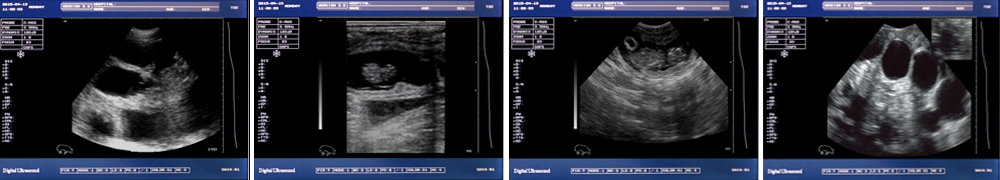

高清分辨率彩色液晶顯示屏,圖像更清晰